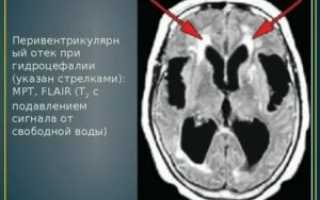

Перивентрикулярный отек у новорожденного

Отек мозга — это такая патология, при которой циркуляция жидкости внутри черепа нарушена, что может привести к сильному давлению на ткани и отмиранию клеток.

Особо тяжелые случаи могут спровоцировать развитие ДЦП и эпилепсии. Перивентрикулярный отек приводит к развитию некроза тканей мозга. Известны случаи летальных исходов, когда поражения головного мозга ребенка были слишком обширными, и лечение оказалось несвоевременным либо неполным.